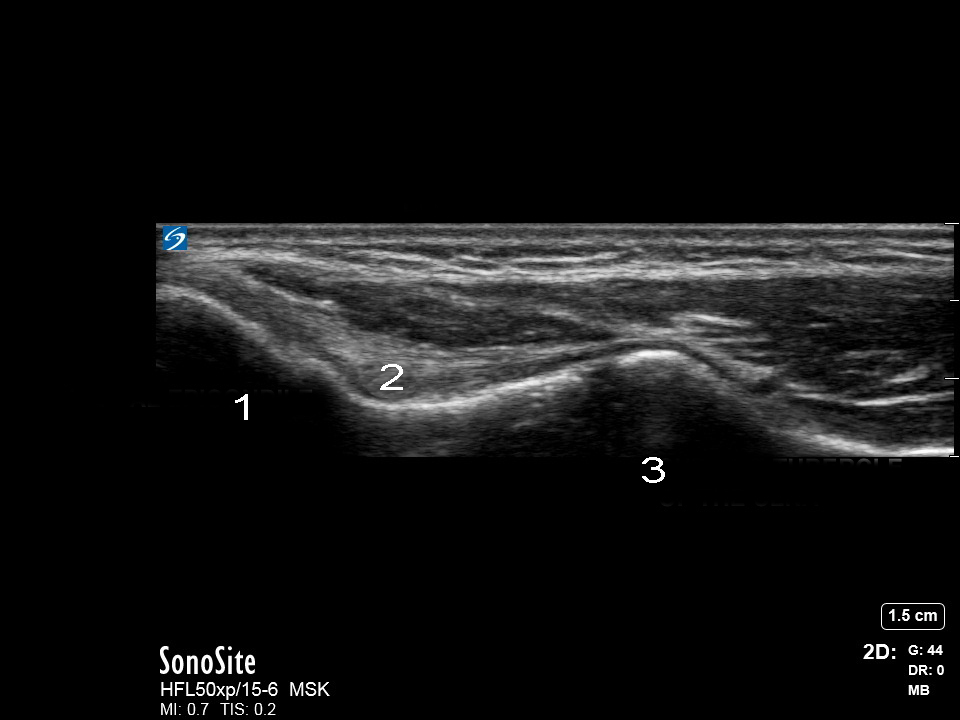

肘尺骨側副靱帯の画像

内側上顆

内側側副靱帯(UCL)

尺骨鉤状結節